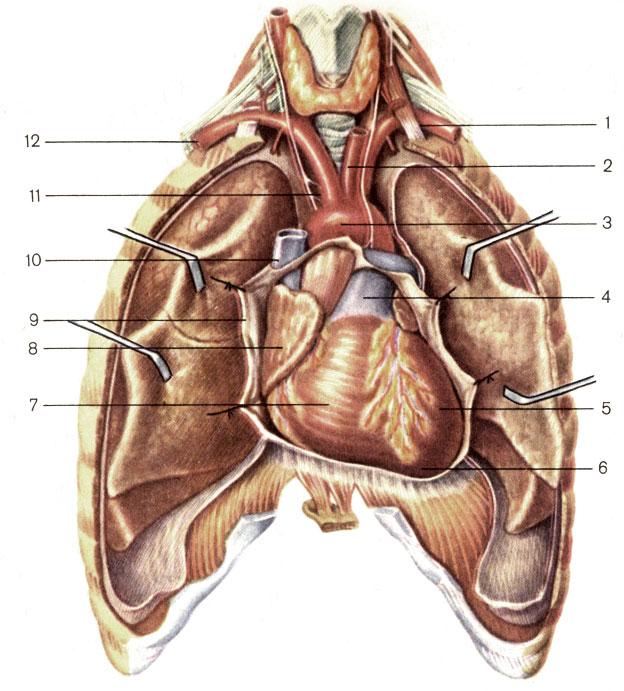

Анатомия Сердца: Расположение и Функции